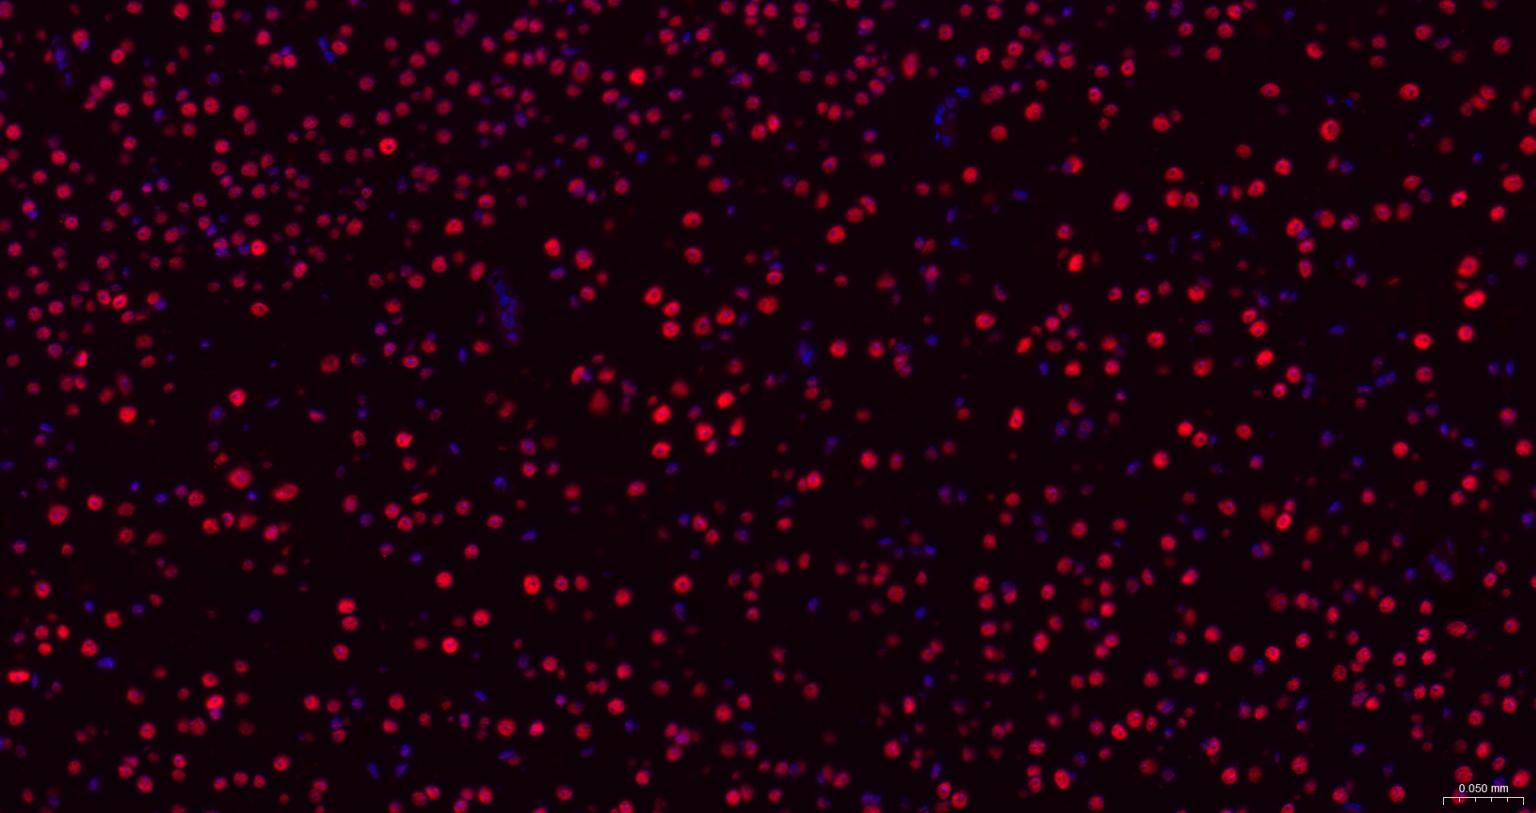

Paraformaldehyde-fixed, paraffin embedded Rat Cerebrum; Antigen retrieval by boiling in sodium citrate buffer (pH6.0) for 15 min; The section was incubated with TARDBP Monoclonal Antibody, Unconjugated (bsm-60837R) at 1:200 overnight at 4°C. Followed by conjugated Goat Anti-Rabbit IgG antibody (Red, bs-0295G-BF594), DAPI (blue, C02-04002) was used to stain the cell nuclei.